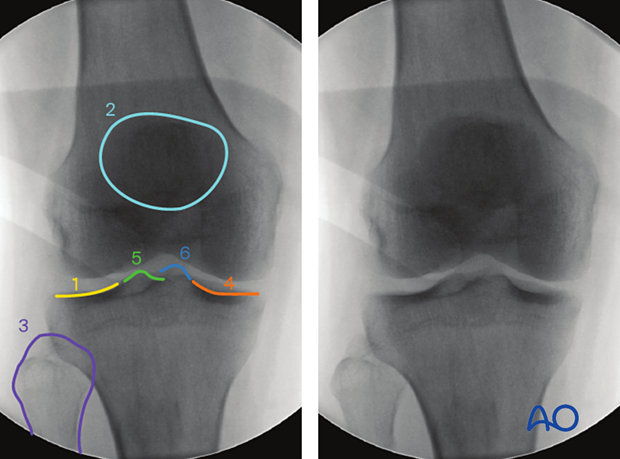

To obtain the optimal AP view of the proximal tibia:

AP images obtained with the knee in 30° flexion will not be very different from those recorded with the leg in full extension.

With the knee in 90° flexion, an AP view cannot be obtained.

The optimal AP view of the proximal tibia is obtained when:

The following lines and landmarks can be observed in the AP view of the proximal tibia:

This view is particularly useful to identify:

The correct angle between the joint line and the tibial axis (85-90°)

Images of the contralateral side may be beneficial as a reference.